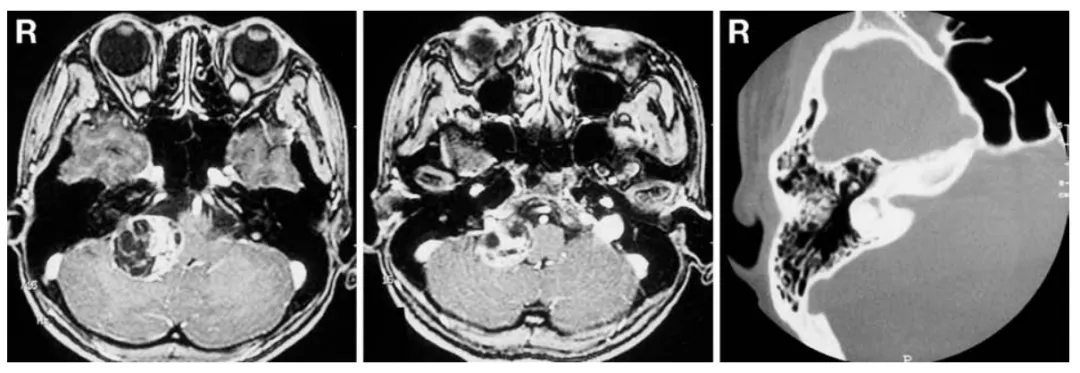

29岁女性患者小葵因听力丧失就诊,无其他神经功能缺损表现。初次磁共振成像检查显示右侧桥小脑角区存在直径3.5厘米囊实性强化占位病变,压迫脑干结构,但未明显侵犯内耳道或颈静脉孔(图1左、中)。骨窗计算机断层扫描检查显示内耳道无明显扩张(图1右)。

图1:术前轴位增强T1加权磁共振成像(左、中)显示右侧桥小脑角区占位性病变,未明显侵犯颈静脉孔。术前骨窗计算机断层扫描(右)显示内耳道无明显扩张。

幸运的是,患者小葵在出院前实用听力已恢复。术后1周纯音听阈测定证实其听力恢复(图2右)。术后8个月磁共振成像复查显示未见肿瘤复发(图3)。

图3:术后8个月轴位增强T1加权磁共振成像显示肿瘤无复发。